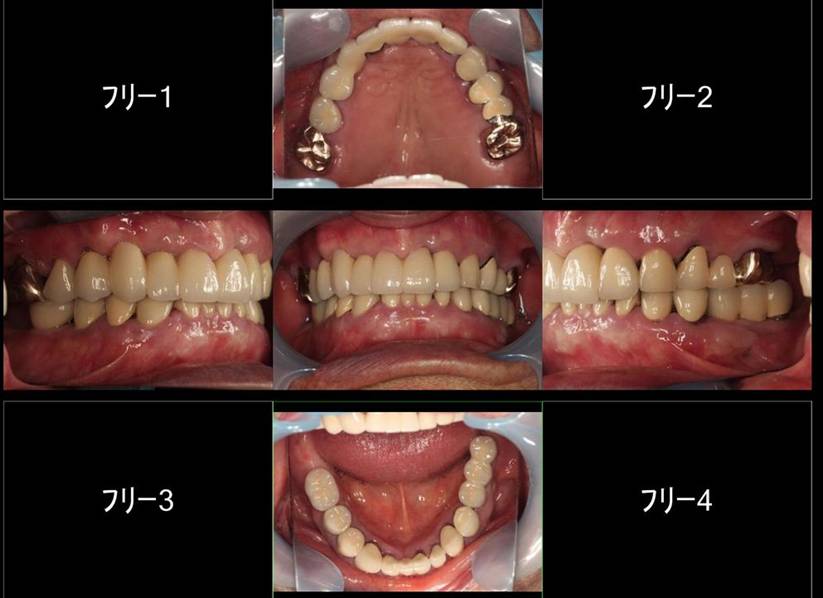

よく噛めなかったケース

術前。62歳男性。仮の歯の入っている上顎前歯部は抜歯するしかない状態。右下がない為右上臼歯が伸びだしていました。入れ歯では咬めないのでインプラントを希望され紹介されて来院されました。

63歳術後。よく噛めるようになり喜んでいただけました。

術前のパノラマレントゲン写真。仮歯を支えている4本の歯は根が残っているだけで抜歯の必要がありました。

63歳術後のパノラマレントゲン。インプラントはスプラインツイスト

664年後

719年後

664年後、右下の小臼歯が破折していました

71歳、9年後。破折した右下にインプラントを追加しています

ストローマンインプラントとスプラインインプラント

ストローマンインプラントとスプラインインプラントが隣り合わせに埋入されています.このころストローマンからスプラインに変えています。変えた理由は前歯部の審美性に優れていること、アバットメントの自由度があること、抜歯後すぐに埋入できるなどでした。

6年後。犬歯にコンポジット充填。第一大臼歯はメタルボンドになりました

8年後ほとんど変化がありません

8年後メタルボンド、反対側はジルコニアクラウン

12年後